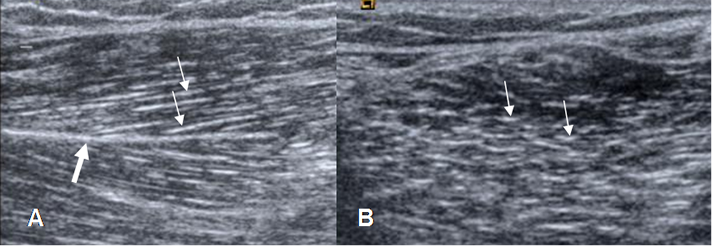

En la ecografía se identifica el perimisio, como imágenes paralelas y ecogénicas en los cortes longitudinales y como rayas cortas, en los axiales. El epimisio también es una estructura ecogénica. (3). (Fig 2).

Dentro de los músculos se aprecian otras bandas ecogénicas, que corresponde a los septos intramusculares. (Fig 2).

Fig 2. Músculo normal.

A: Ecografía corte longitudinal y B: corte transversal. Arquitectura normal, con perimisio ecogénico (Flechas delgadas). También se identifica un septo intramuscular ecogénico (Flecha gruesa).